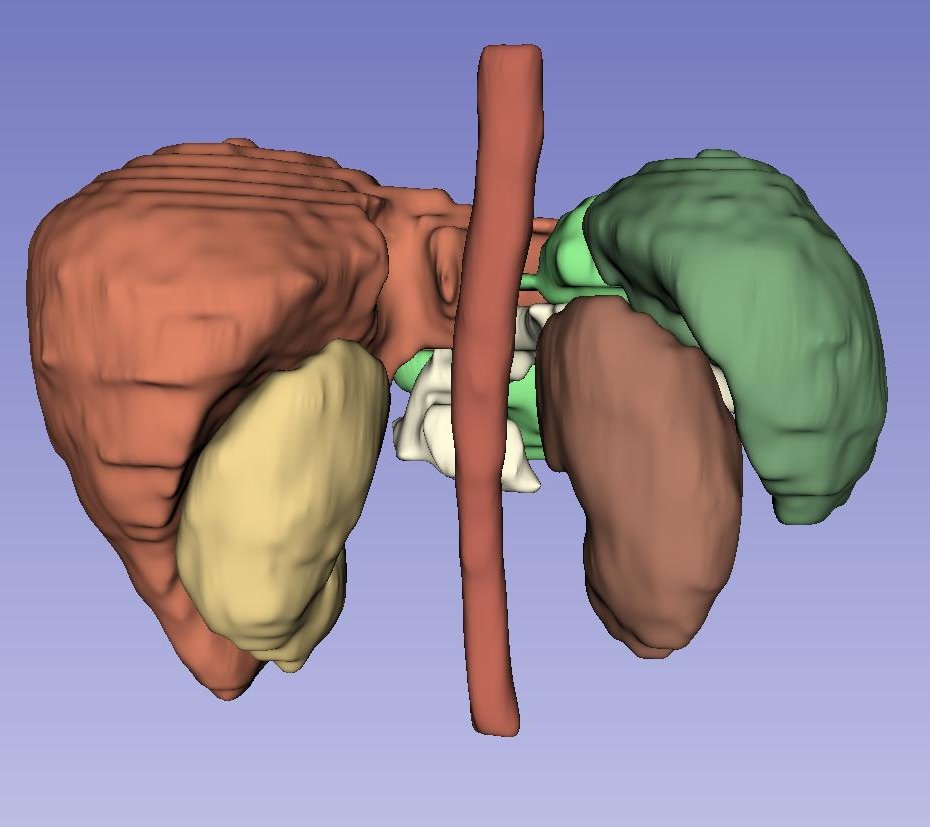

Left Atrial Dataset (LA): Figure˜5 presents a qualitative, three-dimensional visualization of various models’ performance in segmenting the Left Atrial dataset for individual patients. Each row in the figure is dedicated to the segmentation results from a single patient’s dataset, visually assessing each model’s predictive capabilities. In the case of the first patient, shown in the top row, all models except UNETR manage to generate a single entity segmentation, highlighting their ability to integrate disparate anatomical features into a unified model prediction. However, a common challenge across all models is the accurate segmentation of the right corner of the atrium, suggesting a shared area of potential improvement. For the second patient, delineated in the second row, it is discernible that competing models struggle to accurately segment the entirety of the ground truth, resulting in multiple segmented instances rather than a single cohesive structure. Contrarily, LHU-Net succeeds in rendering a single, contiguous segmentation that closely resembles the ground truth, demonstrating its ability to produce smoother and more coherent segmentations. The last patient, as illustrated in the bottom row, presents a challenging case where all models exhibit a tendency for over-segmentation at the base of the atrium. This is indicative of the intrinsic complexity of accurately delineating this anatomical region. Nevertheless, it is worth noting that certain models, specifically UNETR and SwinUNETR-V2, additionally exhibit under-segmentation in other areas, further complicating the segmentation task. In summation, the visualizations in Figure˜5 suggest that LHU-Net consistently generates more robust and smoother segmentations, avoiding the creation of extraneous entities.